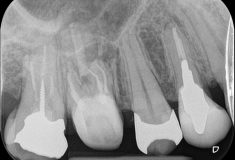

今回の症例は右上の6番目の歯の治療です。レントゲンを撮影すると根っこの先に黒い影ができております。

これは、歯の中で細菌が増殖し、体との免疫反応で骨が溶けている状態です。

②そのうちの一つに大きな根尖病変がある

③その根っこの先に治療の器具が折れている

②はCT撮影でしっかりと確認することができるので、どの根っこが悪いのか、その根っこのどこが悪いのかを診断します。今回はほっぺた側の手前の根っこの先に病変があることがわかりました。